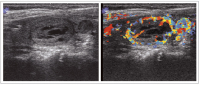

Karzinom

Abbildung 12a-b: Karzinom. a: Querschnitt durch den linken Schilddrüsenlappen. b: Der unscharf begrenzte echoarme Knoten zeigt dopplersonographisch eine deutlich gesteigerte Perfusion. Histologischer Befund: Medulläres Schilddrüsenkarzinom.

Keywords: KarzinomOnkologieSchilddrüse